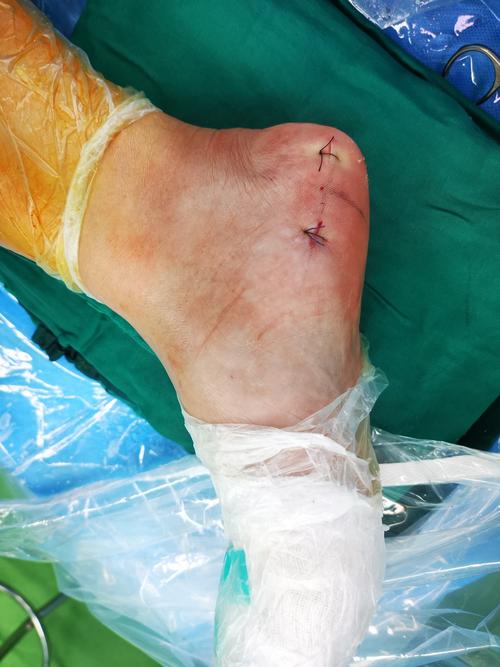

关节镜下切除跟骨骨刺治疗顽固性足跟痛

保康县人民医院成功开展首例关节镜下微创治疗跟痛症|骨刺|手术_网易